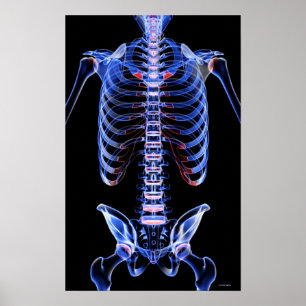

Bones of the Trunk 2 Poster

Price$40.80